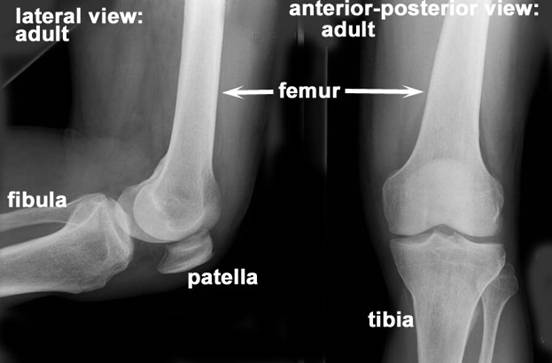

Radiografia genunchiului - lateral

Pacientul in DL; fata laterala a genunchiului de radiografiat se reazema pe caseta; genunchiul sanatos, in flexie, este trecut inaintea membrului examinat.

RC perpendiculara pe caseta; intra la partea anterioara a interliniei articulare. Film de 18x24 cm, in lung, marginea proximala a casetei la un lat de mana deasupra nivelului rotulei; marginea anterioara la doua laturi de deget de fata anterioara a rotulei.

Distanta F-F = 1m; fara Bk.

Radiografia genunchiului lateral si A-P